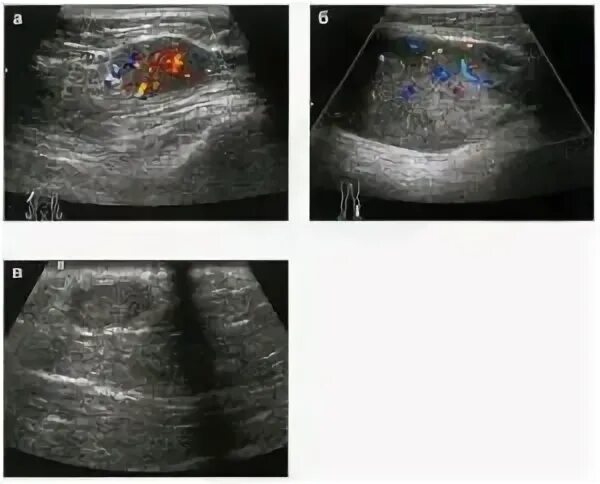

Метастазы в молочной железе прогноз